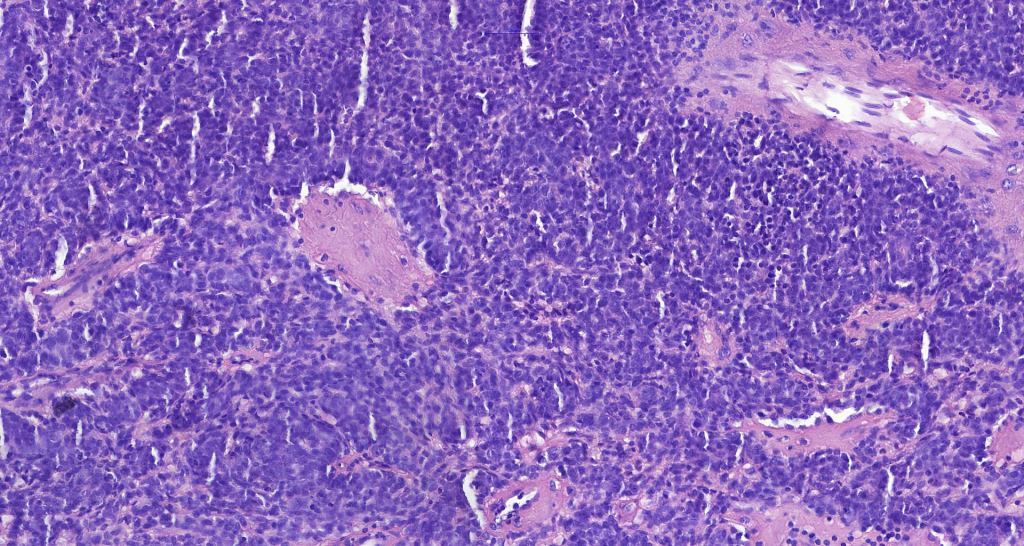

Histological features

•Nodule/multiple blue encapsulated nodules in the dermis +/- subcutaneous fat

•Common association with an adjacent nerve & exceptional intraneural component

•Outer layer of small intensely basophilic cells surrounding larger pale staining or eosinophilic cells with vesicular nuclei & small nucleoli

•Intra-tumoral lymphocytes

•Ductal & exceptionally, glandular differentiation

•No pleomorphism & only sparse mitoses or no mitoses

•Basement membrane thickening & intralobular eosinophilic globules